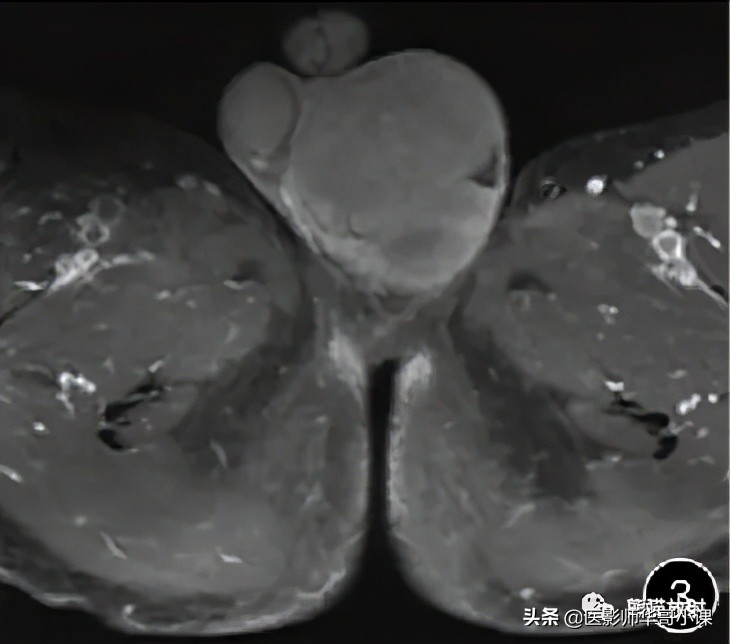

![[精品课件]畸胎瘤及精原细胞瘤(*丸睾**肿瘤及肿瘤样变CT及MR表现)](http://static.shicijianshang.com/origin/pgc-image/363432124ff549eb8031031e872b3dfd.jpg)

图5 男,80岁, 双侧*丸睾**脓肿 。双侧*丸睾**肿大,信号不均,其内见液化坏死; 增强扫描可见明显环形强化,与附睾分界欠清,邻近皮肤增厚。